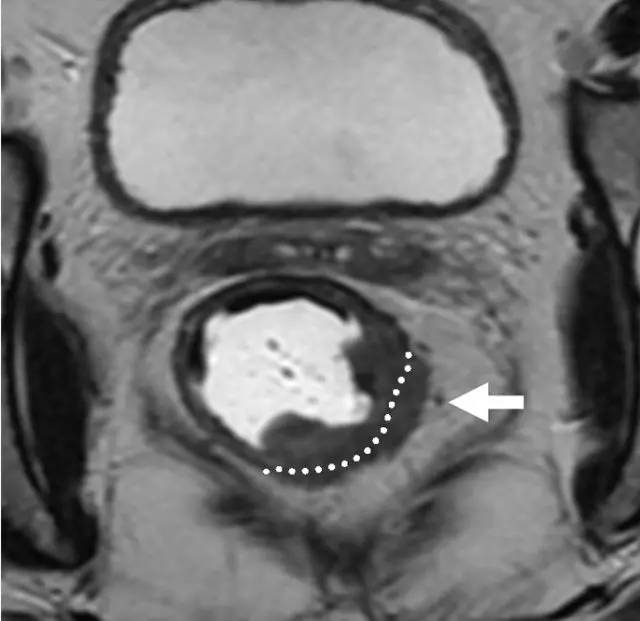

环周切缘 CRM

直肠系膜筋膜是包围直肠周围脂肪和直肠的低信号,代表 TME 切除术中的手术切除平面。在 MR 图像上,是进行 TME 手术患者的潜在 CRM。CRM 阳性是局部复发和预后差的一个重要的独立预后因素。

图 29 轴向 T2 加权图像报告 CRM 的距离。虚线描绘了直肠系膜筋膜,这是 T3a 肿瘤的 CRM,预测 CRM 阴性